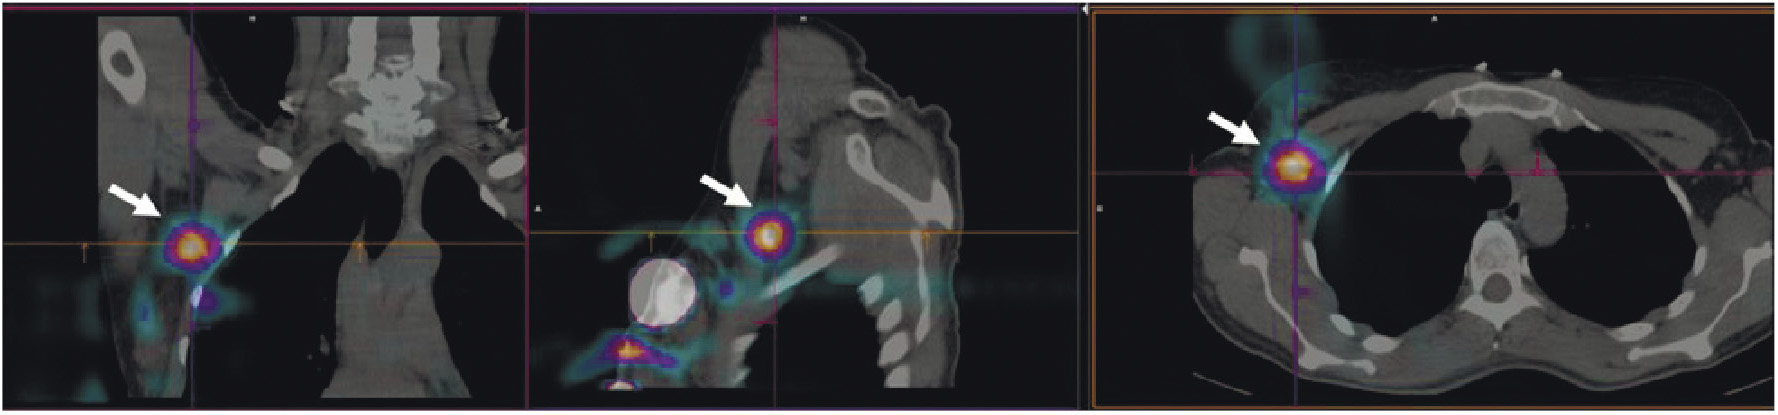

В рутинной клинической практике для ПЭТ/КТ-визуализации опухоли предстательной железы и её метастазов применяются радиофармпрепараты на основе простатспецифических мембранных антигенов, меченных 68Ga ([68Ga]Ga-ПСМА-11, [68Ga]Ga-ПСМА-617, [68Ga]Ga-ПСМА-I&T) либо 18F ([18F]F-DCFPyL, [18F]F-ПСМА-1007) [22, 23]. Главные преимущества меченных 99mТс препаратов, тропных к ПСМА, — невысокая стоимость и доступность технеция-99m, а также возможность визуализации опухоли с помощью гамма-камеры. В настоящее время для этих целей предложен ряд радиофармпрепаратов [24]. В России зарегистрированы наборы для приготовления 99mTc-HYNIC-ПСМА (“ПСМА HYNIC, 99mТс”, Польша; “Проскан, 99mТс”, Россия). Отечественный РФЛП разрабатывался в ТПУ и НИИ онкологии Томского НИМЦ. Клинические испытания 99mТс-ПСМА показали его высокую эффективность при диагностике и стадировании рака простаты, а также при отборе на радиолигандную терапию и оценке её воздействия (рис. 4).

Рис. 4. ОФЭКТ с 99mТс-ПСМА пациента с раком простаты до (а) и после (б) четырёх курсов радиолигандной терапии 177Lu-ПСМА